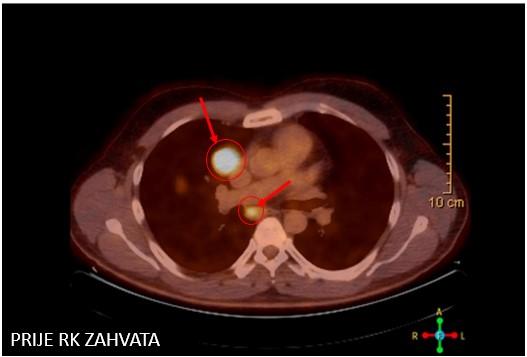

Bolesnica, rođena 1958. Dijagnoza: Adenocarcinoma lobi inferioris pulmonis sinistri